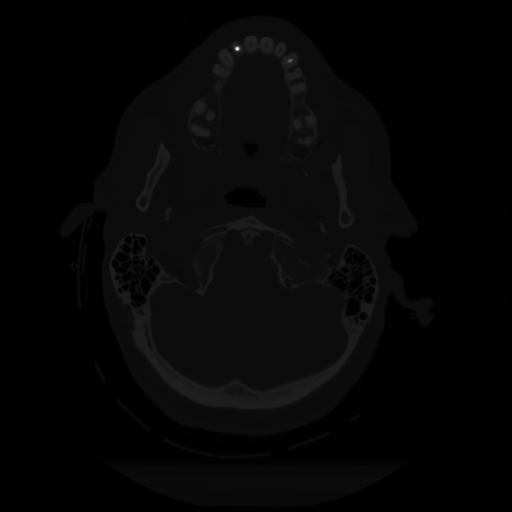

12 P.BLANDAS,,Vol,0.5,P.BLANDAS,,